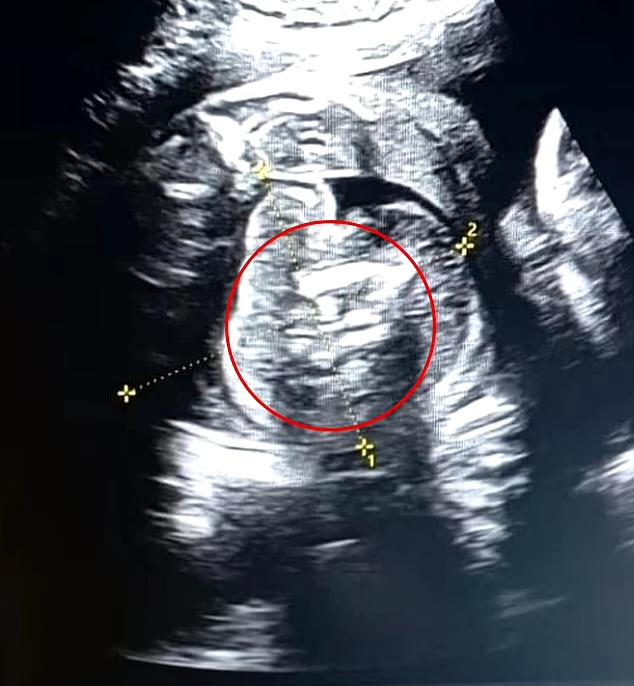

Though her previous scans had come back normal, doctors discovered “an additional structure containing bones” in the unborn baby boy’s abdomen.

Further testing revealed two other malformed fetuses inside the fetus’ abdomen.

Dr Prasad Agarwal, who conducted the scan, told local media: “I was lucky and vigilant enough to notice something very unusual with this baby, grossly normal growing fetus with a few bones and a fetus-like structure in its abdomen.

“It struck me immediately that this is not normal. It was ‘fetus in fetu,’ one of the rarest cases in the world.”